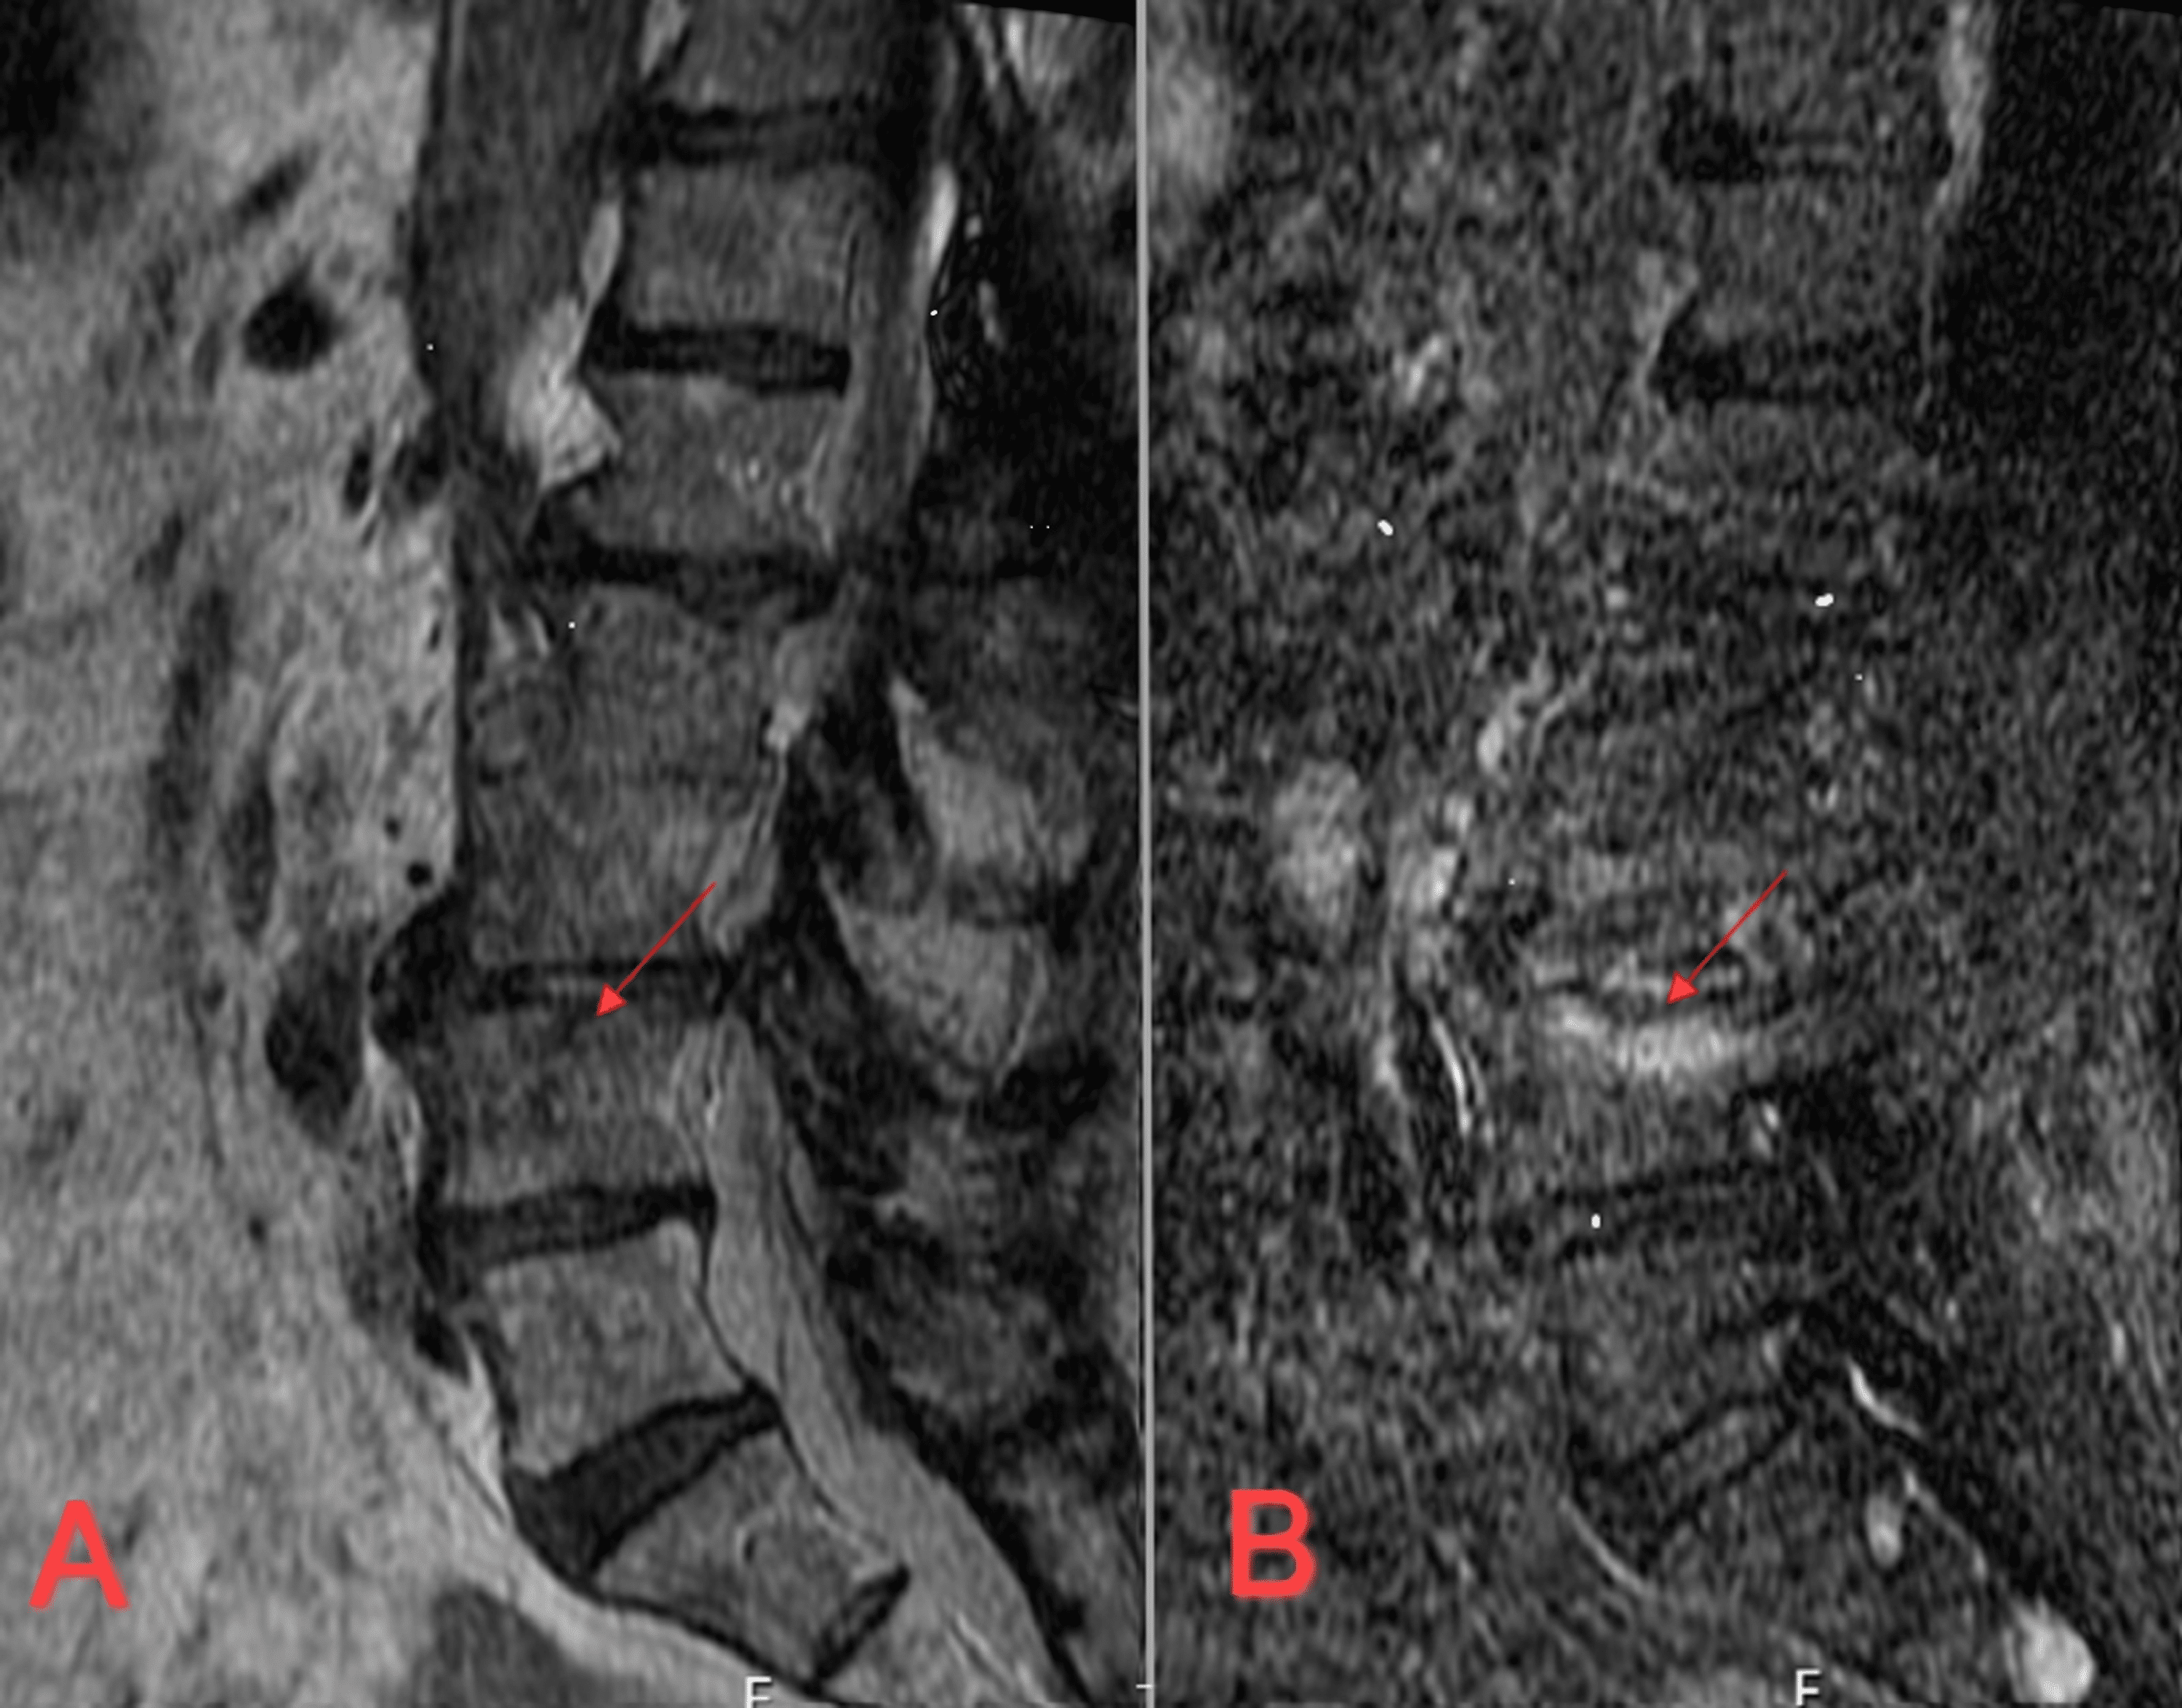

Cureus Lumbar Spine Osteomyelitis After Permanent Spinal Cord Are Spinal Cord Stimulator Permanent It can block pain signals from reaching your brain and reduce your. Activities that add pressure to the body, such as scuba diving more than 10 meters below the surface, are permanently restricted for those with implanted stimulators. Can you go swimming with a spinal cord stimulator? Learn how a spinal cord stimulator can relieve chronic pain by sending low. Are Spinal Cord Stimulator Permanent.